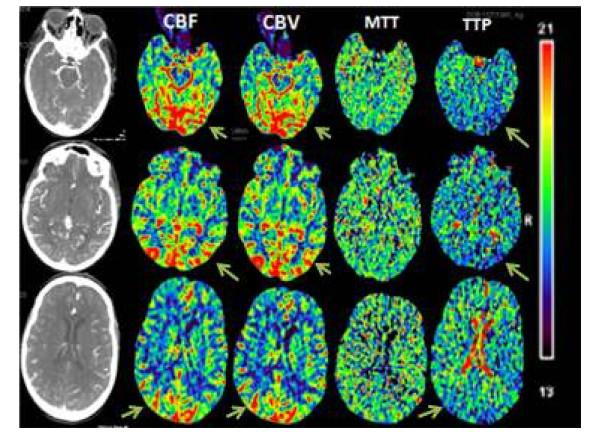

后部可逆性脑病综合征(PRES)与CT灌注改变

Posterior reversible encephalopathy syndrome (PRES) and CT perfusion changes.

Posterior reversible encephalopathy syndrome (PRES) can present with focal neurologic deficits, mimicking a stroke and can often represent a diagnostic challenge when presenting atypically. A high degree of suspicion is required in the clinical setting in order to yield the diagnosis. Cerebral CT perfusion (CTP) is utilized in many institutions as the first line in acute stroke imaging. CTP has proved to be a very sensitive measure of cerebral blood flow dynamics, most commonly employed to delineate the infarcted tissue from penumbra (at-risk tissue) in ischemic strokes. But abnormal CTP is also seen in stroke mimics such as seizures, hypoglycemia, tumors, migraines and PRES. In this article we describe a case of PRES in an elderly bone marrow transplant recipient who presented with focal neurological deficits concerning for a cerebrovascular accident. CTP played a pivotal role in the diagnosis and initiation of appropriate management. We also briefly discuss the pathophysiology of PRES.

摘要